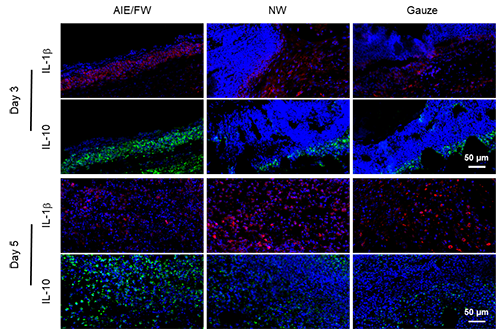

����Ă��ڷ��ϑ��߂��ڰl�׺�ē�[�Ȑ��ӗl�������Ə��s������Ⱦ��������ͬ�r���НBҺ�B���r������Ч���՝B������ܱ��ք������Ȼ������Ҏģ���a��߸�Ч�V�V�������ܺ̓�����ȹ��������ĸ����܂��ڷ���һֱ��һ험O�������Ե��΄����@��о������菽�����Ȍ������S���ҭh���Ѻõ���Ȼľ���M�к��ε�Óľ��̎�������������������͸�����Ե����S�ּ���׽Y�������x���䳬���g����ʹ���܉����m�N�����wƤ�w���D1�����ڴ˻��A�����о��ˆTᘌ��Ե��OӋ�ϳ��˹������֦������늺ɵ�AIE�������ӣ�DTCSPYSi����ԓ���Ӳ��H���и�Ч�Ļ������a��������չ�F�������Ĺ����������������������С�������܉��cľ���ι̽Y�ϣ��D2-4�����о��ˆT���������DTCSPYSi�ď�����Ч���͵ͼ������ԣ���Ч�A�������Ⱦ���p�p�װY������ͬ�r���Y��DTCSPYSi����ˮ�����Լ�ľ��͸��͸���������{��Ĺ��Ќ���������������ṩ��һ���m�˵ĝ�h����ͨ�^����������ί��͝�ȹ����ąfͬ���ã����F���pЧ���M��ˎ����Ⱦ���ڿ������ϵ�Ч����

ľ�Ľ��^Óľ��̎����������¶�������S���Ļ��Թ��܈F���@���������c������늺ɺ͹�������F��DTCSPYSi�l���໥��������ˣ�ͨ�^���εĽ��n̎�������Ɍ�AIE������������ľ�ļ����ڽY������K�õ���AIE/FW�������g�H�w�����m�N�ϣ��D4�������и��_99.73%�ĸ�Ч����������������m�˂������ϵ�����͸���ԣ��Լ����������������ԣ��D5����ͨ�^����������͝�ȹ����ąfͬ������AIE/FW�����܉���Ч�s�̸�Ⱦ���ڵ��װY�������M�M����ֳ�������@���s�̂����������ڣ��D6��7����

�D6. AIE/����ľ�����ڷ�������ˎ����Ⱦ����ģ���е��w������Ч�����M���W�u�r��

�D7. AIE/����ľ�����ڷ�������ˎ����Ⱦ����ģ���е����ߟɹ��װY������